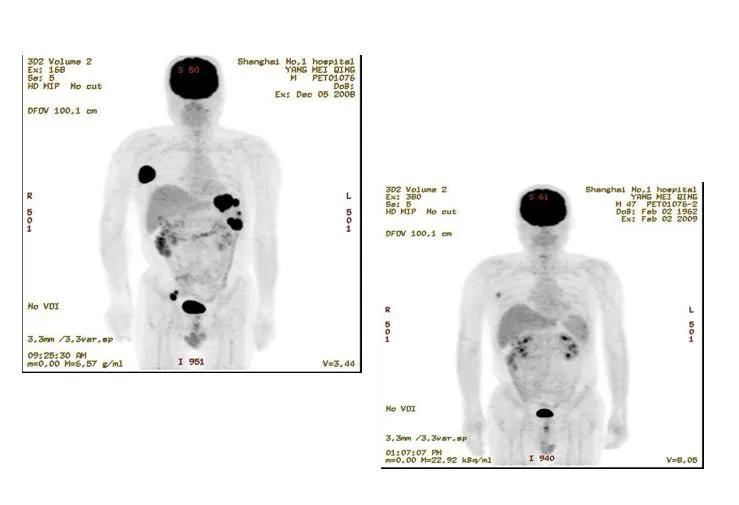

第一例患者,男性,47岁,2007年8月身体多处发现肿大淋巴结(双侧颌下、颈部、颌下、左锁骨上、右气食沟、纵、双侧腋下);脾脏多发占位,肝门部、脾门处、胰周及腹膜多个肿大淋巴结;淋巴结活检确诊非霍奇金淋巴瘤,DLBCL。接受了10次化疗方案(RCHOP/CHOP/MINE/ESHAP)。

2008年7月出现反复腰背部疼痛,腰椎CT见腰4椎体病理性骨折可能,腰3/4、腰4/5椎间盘膨隆。综合各项检查考虑骨转移,给予双磷酸盐治疗,腰椎+后腹膜淋巴结放疗。2008年11月给予重组人血管内皮抑制素(恩度)+健择+奥沙利铂+Pred 方案治疗。但该例患者使用多个化疗方案治疗效果都不好,在治疗过程中病情还在进展,出现新的病灶。

针对该例难治的患者,王教授团队进行了自体造血干细胞移植。把正常造血干细胞采出来冷冻保存,同时患者接受化疗减低肿瘤负荷,然后行造血干细胞移植。移植后,结合局部放疗和美罗华维持治疗。患者治疗效果满意,淋巴瘤至今仍为缓解状态。

第二例患者,男性,44岁,2008年8月因“右上臂疼痛不适”入住当地医院,影像学检查提示右肱骨上段占位,予行右肱骨上段肿瘤切除术+右关节假体置换术,术后病理示弥漫大B细胞淋巴瘤。2009年1月发现右侧鼻梁皮下肿块,行CT检查示右侧上颌窦占位。行右侧皮下肿块穿刺细胞学检查,见恶性肿瘤细胞,倾向非霍奇金淋巴瘤。移植前接受了6个疗程化疗以及19次放疗,但病情仍在进展,出现新的腰椎病灶。

王椿教授指出,从该例患者可以看出,淋巴瘤是一个全身性疾病,所以治疗一定是全身性治疗,所以患者同样接受了高剂量化疗联合自体造血干细胞移植治疗,治疗后疾病达到缓解。